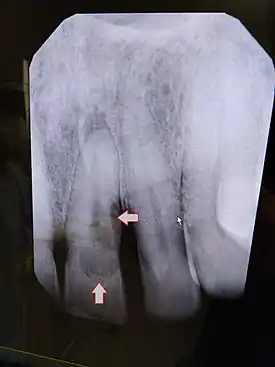

| Post traumatic External tooth resorption 9 | |

| Diagnostic method | Dental examination, X-rays |